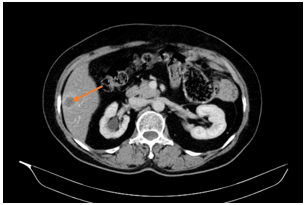

- CLVT lồng ngực – ổ bụng:

Hình 1. Nhu mô gan phải có nốt ngấm thuốc kém chủ yếu ngấm viền ngoại vi đường kính ~ 25mm